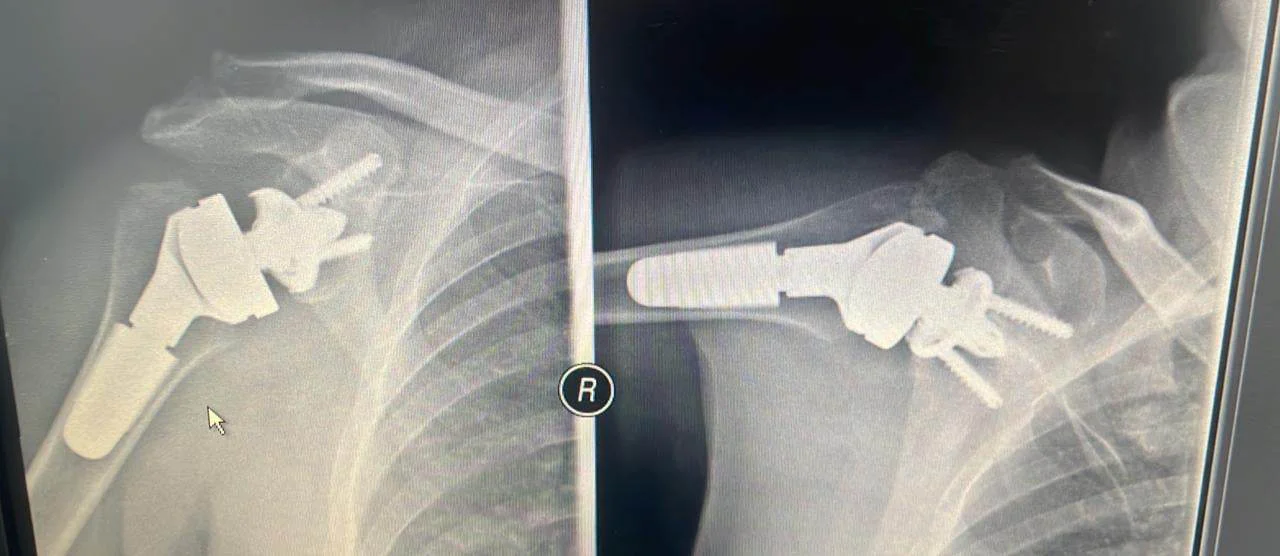

Η ασθενής υποβλήθηκε λοιπόν σε ανάστροφη ολική αρθροπλαστική του ώμου, η οποία αφορά την εμφύτευση τεχνητών επιφανειών στην άρθρωση του ώμου οι οποίες τοποθετούνται αντιστρόφως.

Πιο συγκεκριμένα, το μεταλλικό ημικύκλιο της σφαίρας που αντικαθιστά την κεφαλή του βραχιονίου οστού, τοποθετείται στην ωμογλήνη, την υποδοχή της ωμοπλάτης. Το πρόθεμα αυτό σταθεροποιείται αρχικά με μία πανίσχυρη κεντρική βίδα καθώς και ειδικές περιφερικές βίδες. Στη συνέχεια τοποθετείται ένας  ένας στειλεός στο βραχιόνιο. Αυτά κουμπώνουν μεταξύ τους με ένα πλαστικό πολυαιθυλένιο. Με αυτό τον τρόπο λοιπόν έχουμε  ένα εξαιρετικά δυνατό και σταθερό νέο ώμο, ο οποίος επιτρέπει την κίνηση προς κάθε κατεύθυνση και δύναται να πάρει οποιοδήποτε φορτίο. Εμβιομηχανικά, μετατοπίζεται το κέντρο περιστροφής της άρθρωσης προς τα κάτω και προς τα έξω, βελτιώνοντας έτσι την τάση του δελτοειδούς μυός, αλλά και των παρακείμενων ιστών, μαλακών μορίων και μικρών τενόντων του ώμου, του λεγόμενου στροφικού πετάλου.